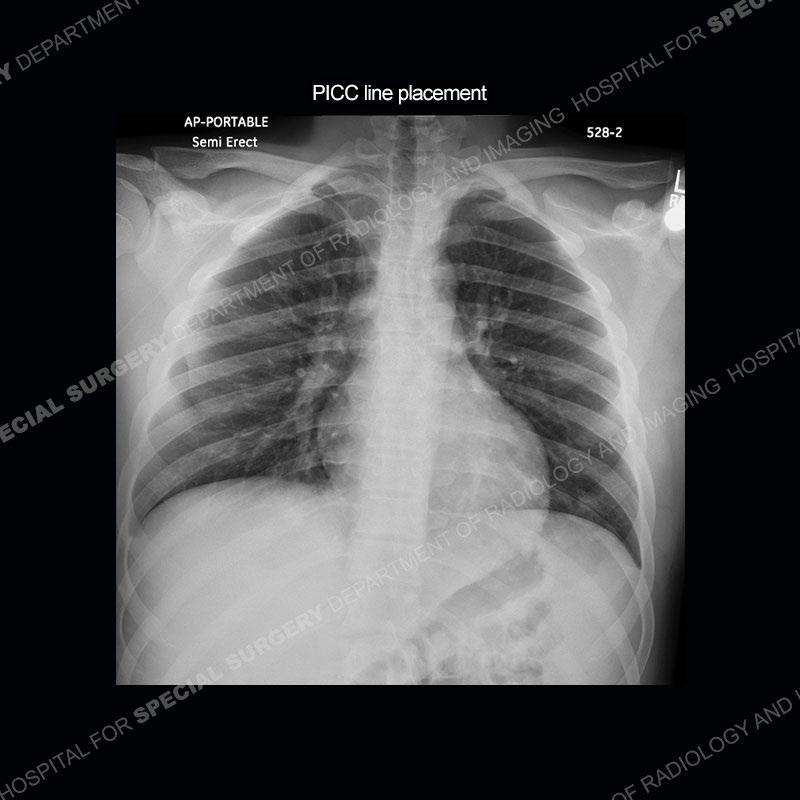

The repeat MRI, with the marked degree of increased abnormality of the bone and soft tissue shifted the diagnosis to a high degree towards infection. Even the most aggressive of neoplasms would not have that the degree of change in a 3-day time span. The CT study was shown before the repeat MRI but actually occurred just after the repeat MRI. It helped confirm the destructive process of the ramus and particularly the abnormal architecture along the inferior margin. The patient went on to have a CT guided aspiration of one of the soft tissue collections with 4cc of purulent fluid obtained. A surgical irrigation and debridement of the bone and soft tissue was performed. A PICC line was placed and the patient is currently undergoing IV antibiotic treatment with a possible repeat irrigation and debridement.